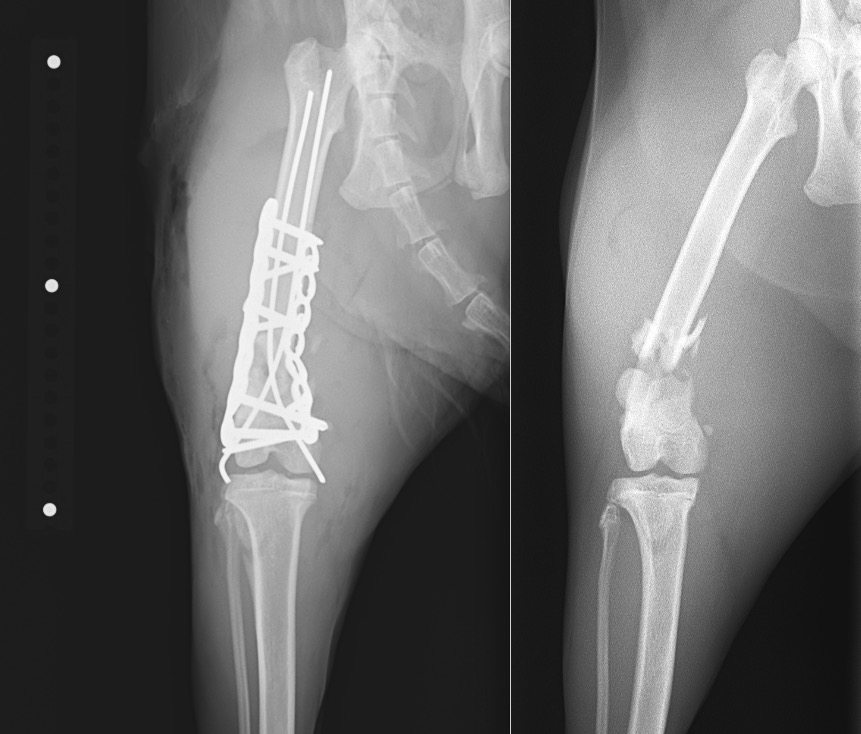

右の大腿骨(太ももの骨)の遠位(膝の関節に近い部分)が粉砕骨折(骨片が3つ以上に砕けてしまう骨折)してしまっていました。

正常肢と比べると、膝の関節に近い部分の骨が折れてしまっているのが分かります。

外科療法は内外側から2本のピン(髄内ピン、ラッシュピン)を挿入し、外側に2.4㎜ロッキングプレート(LCP)、内側に2.0mmロッキングプレート(LCP)を設置、強固な固定を目指しました。

右後肢側面像 術後/術前

右後肢正面像 術後/術前